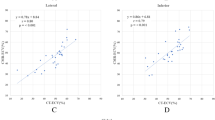

On first-pass CT images, the patients with CA exhibited a significantly lower SNRmyoc than the control subjects (Table 3). Myocardial attenuation was non-significantly lower in the patients with CA (p = 0.1). Blood pool attenuation, SNRblood and CNRblood-myoc were in the same range for both groups. On delayed CT images (Table 4), myocardial attenuation and SNRmyoc were significantly higher in the patients with CA than in the control patients. Blood pool attenuation and SNRblood were in the same range for both groups and consequently CNRblood-myoc was significantly lower in the patients with CA. The mean value of the RAI was 0.12 ± 0.25 in patients with CA. It was positive in all but two and reflected the increase in myocardial attenuation between first-pass and delayed images. In contrast, all the control patients exhibited a negative value of the RAI (mean value −0.56 ± 0.21) because their myocardial attenuation decreased between first-pass and delayed acquisitions. It was statistically (p < 0.05) lower than that of the patients with CA. Images of patients with CA and control patients are reported in Figs. 1, 2 and 3.

The ROC curve and Youden’s test identified an optimal threshold of −0.32 for the relative attenuation index (AUC, 1; 95 % CI [1]; p = 0.0001) as the best threshold for predicting cardiac involvement on MDCT. Sensitivity and specificity of the −0.32 threshold value to predict cardiac involvement were 100 % and 100 %, respectively. Weak but significant negative correlations were observed between myocardial attenuation measured on first-pass images and anterior wall thickness (r = −0.46; p = 0.03), inferior wall thickness (r = −0.45; p = 0.04), interventricular wall thickness (r = −0.43; p = 0.05) and lateral wall thickness (r = −0.66; p = 0.002). No significant correlation was detected between myocardial attenuation measured on delayed enhanced images and wall thickness. No significant correlation was found between MR parameters reflecting myocardium signal on LGE images (SI and SNRmyoc-MRI) and CT parameters. LVEF was weakly correlated with CNRblood-myoc (r = 0.56; p = 0.06).